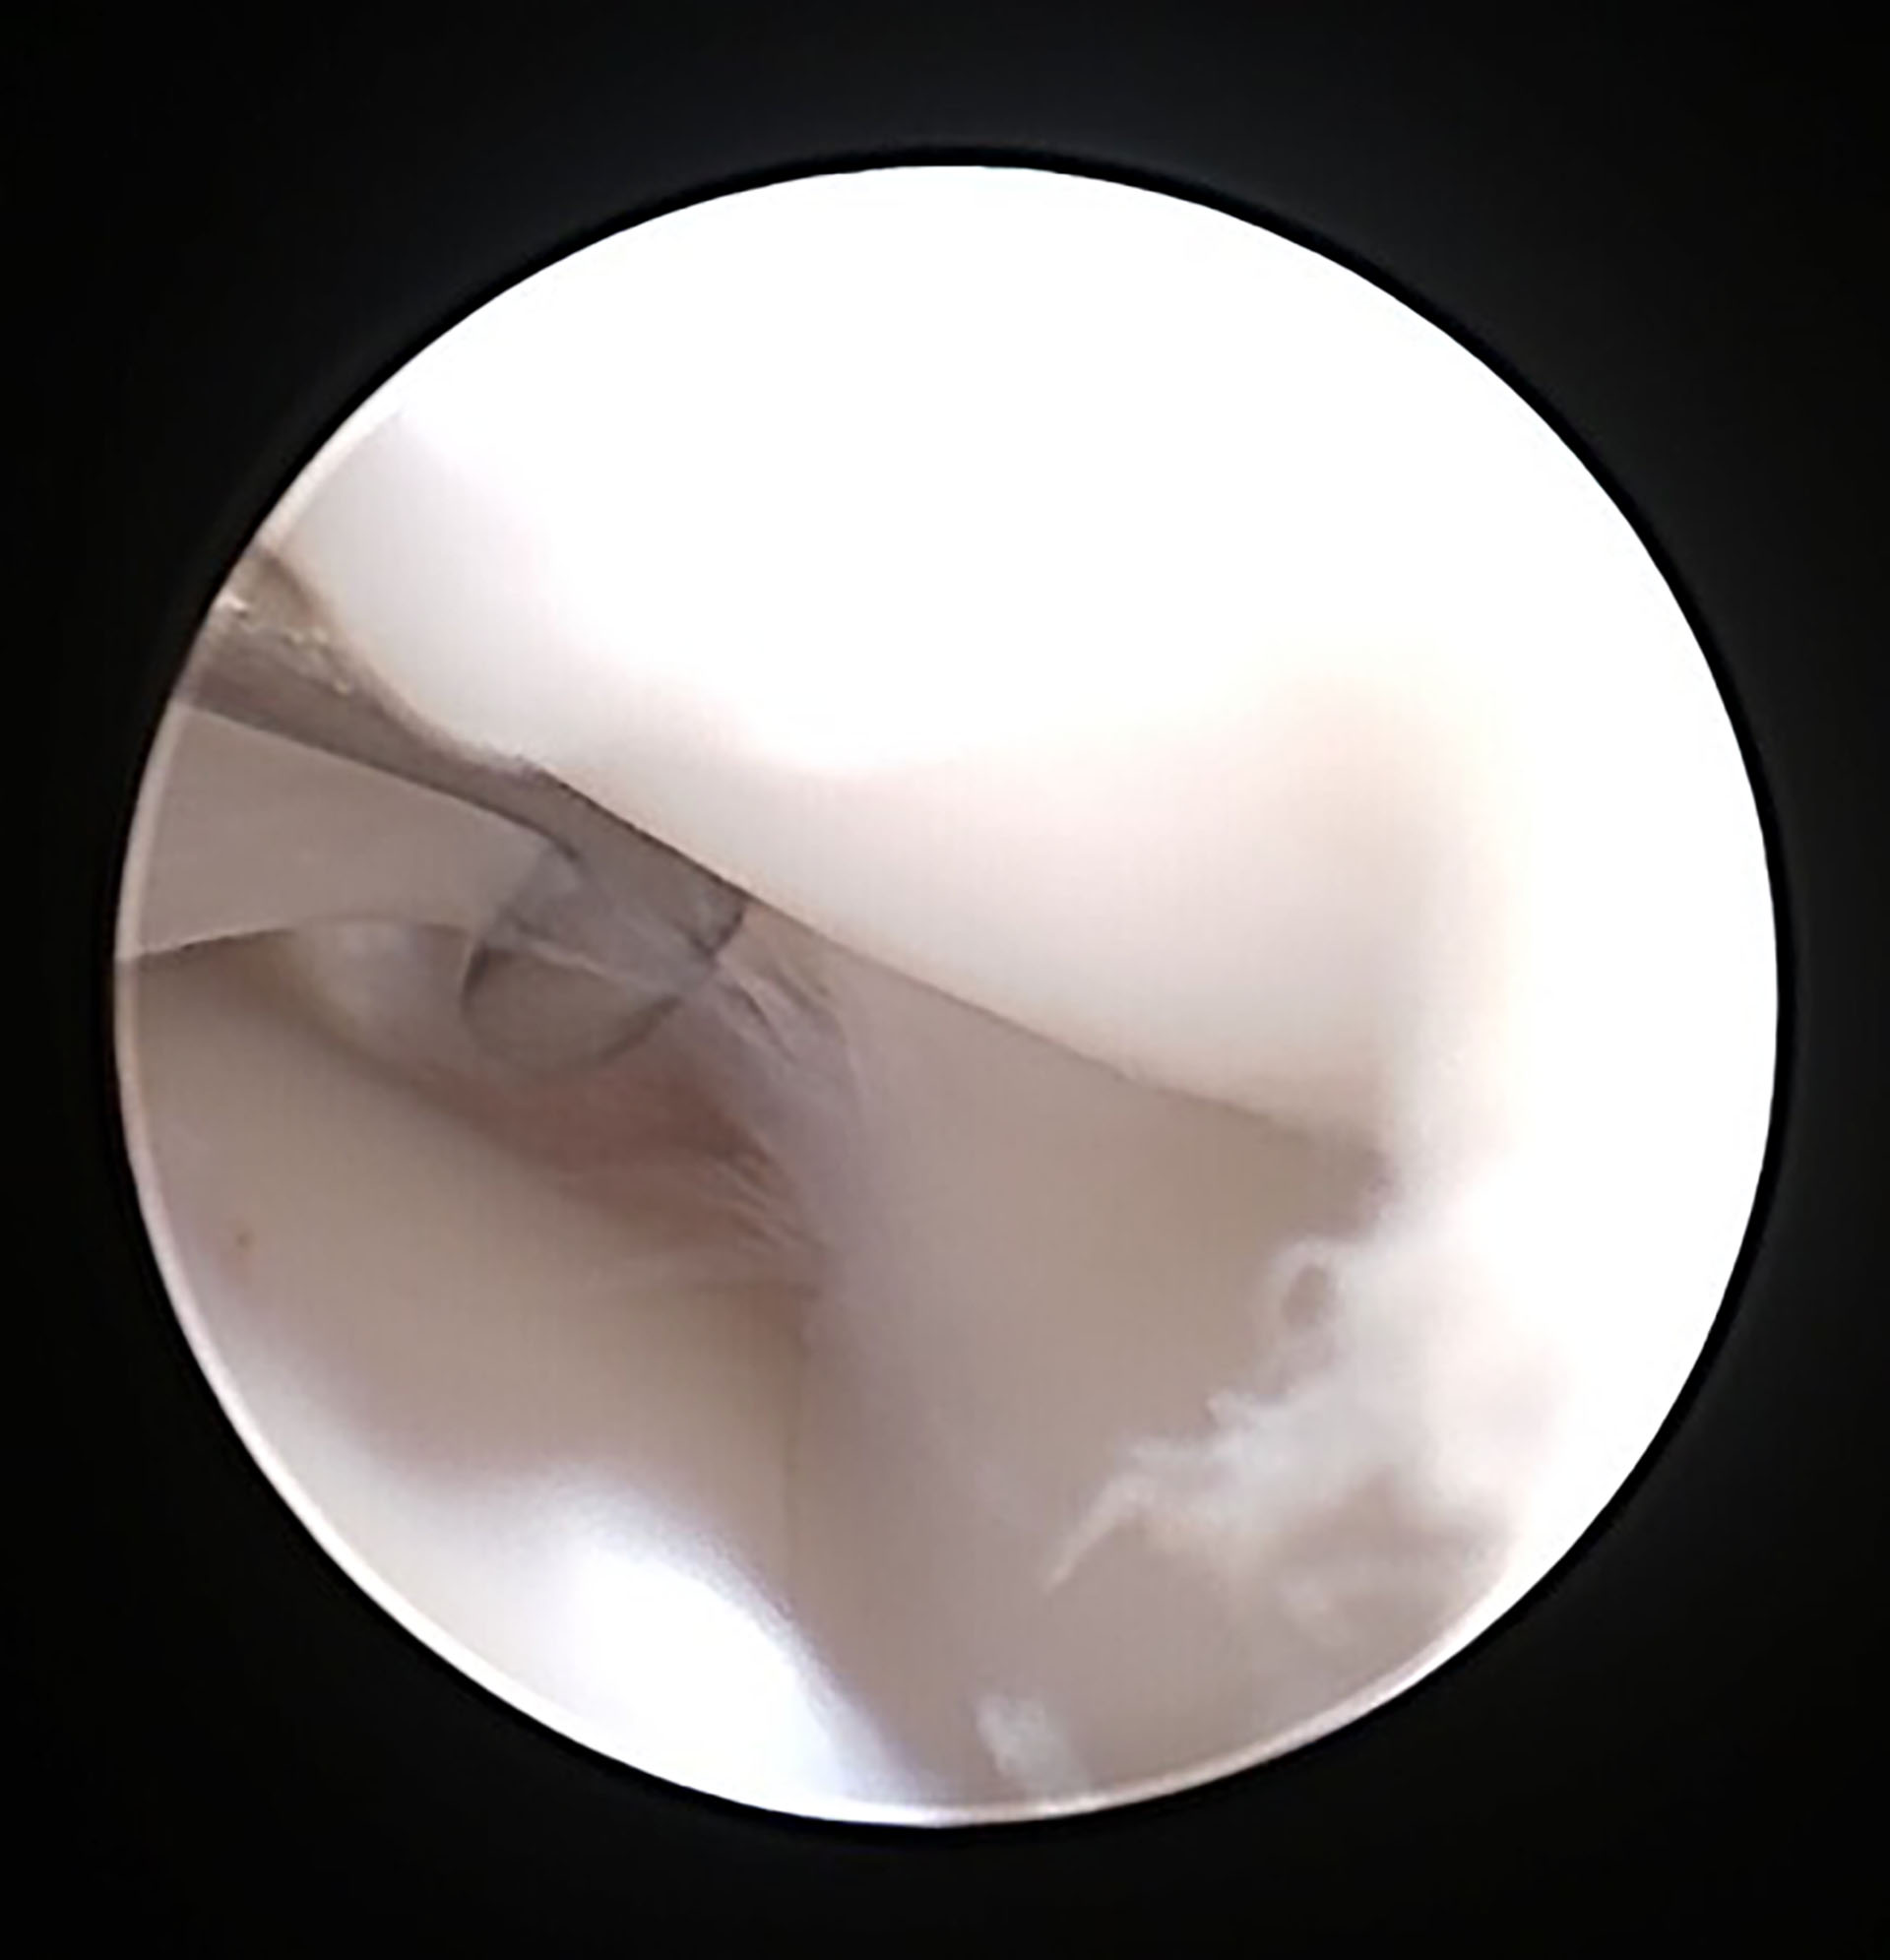

Det ble først utført en eksplorativ artroskopi av venstre kneledd med et 4.0 millimeter skop. Det ble brukt en Leipzig distractor for å bedre artroskopisk vurdering av menisken. Det ble tydelig visualisert at det kraniale korsbåndet var røket (Figur 5), men det kaudale korsbåndet og menisken var uten patologi. De frynsete endene av det kraniale korsbåndet ble debridert med en torpedo shaver.

Figur 5. Artroskopisk bilde av røket korsbånd.

Ved klinisk undersøkelse av denne hunden kunne vi kjenne hevelse medialt for kneleddet, og en positiv kranial skuffetest og tibia kompresjonstest. Det kunne kjennes i både våken og sedert tilstand. Hun viste også tydelig ubehag ved manipulering av leddet. En kranial skuffetest vil si en overdreven kraniokaudal bevegelse av tibia og femur. Når en tibiakompresjonstest utføres hos en hund med korsbåndsskade vil tibial tuberosity beveges kranialt når hasen er i fleksjon og gastrocnemius muskelen kontraherer. Ved korsbåndsskade vil bildediagnostikk hjelpe med å utelukke andre årsaker til bakbenshaltet og er nødvendig for planlegging av en TPLO operasjon. Det ble utført en røntgenundersøkelse av denne hunden etter klinisk undersøkelse av både høyre og venstre bakben. Radiografiske forandringer som kan sees ved ruptur av korsbåndet og kronisk skade er tap av intrapatellar fettpute skygge, ekstensjon av den kaudale leddkapselen på grunn av leddeffusjon og osteofyttdannelse ved trochlear ridge, tibia kondylene, intercondylar notch og distale del av patella. Det var tydelig tap av intrapatellar fettpute skygge, leddeffusjon og osteofyttdannelse på røntgenbildene av venstre bakben hos denne hunden. En god del av overflaten til korsbåndet kan bli eksaminert ved hjelp av artroskopi. Det som kan sees er ruptur av korsbåndet, fibrillering, og fargeforandringer. Meniskene kan også bli vurdert. En artroskopisk undersøkelse er en minimal invasiv teknikk som gir en grundig vurdering av kneleddet, i tillegg er det en stor fordel med god belysning og forstørrelse av strukturene. Det ble utført på denne pasienten, hvor det tydelig kom frem at det kraniale korsbåndet var helt røket av. Det kaudale korsbåndet og menisken var ikke affisert. Artroskopi er gullstandard for vurdering av ledd (2).